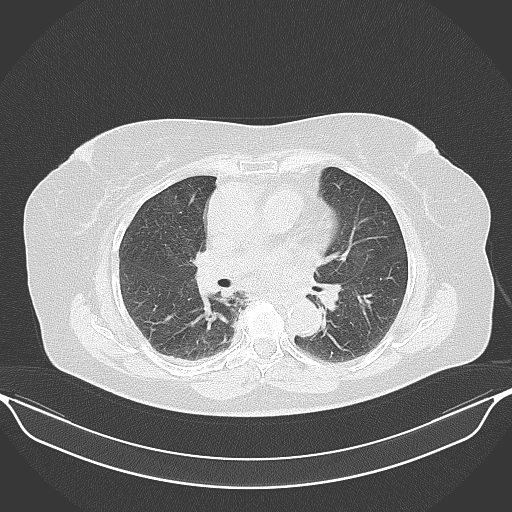

Image Grid

4Γ—3 grid: Rows show different image types (Original NATIVE, Reconstructed NATIVE, Original VENOUS, Generated VENOUS), Columns show windowing techniques (No Window, Lung Window, Mediastinum Window)

Lung window (WL -600, WW 1500 β†’ Low βˆ’1350, High +150)

Reconstructed NATIVE CT scan (cycle consistency)

Original VENOUS CT scan

Generated VENOUS CT scan (A→B translation)